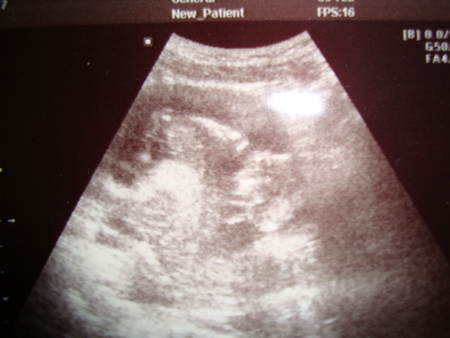

Рост малыша примерно 23,4 см

Вес малыша примерно 280 грамм

Он помахал мне ручкой и гладил себя по щечке. Такой маленький еще, 7,2 мм, а так крутится там,не давал сфоткать сначала себя, прятался))) Такая прелесть, я даже прослезилась немного. Все хорошо у нас, поставили 13 недель и 1 день по месячным, а по УЗИ 13 и 4.